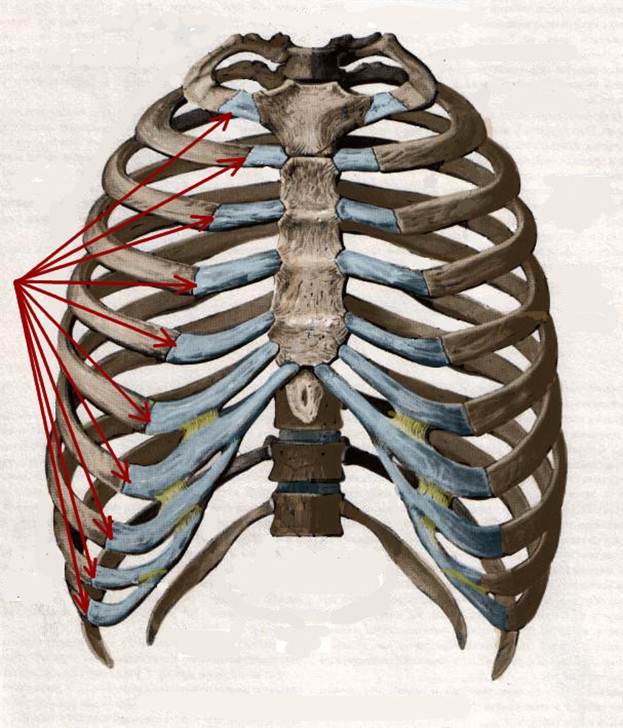

S: Стрелки указывают на сostae verae (латинский язык).